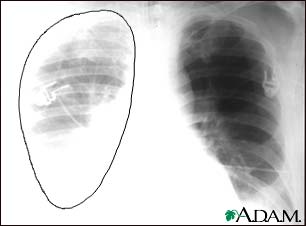

Aortic rupture, chest x-ray

Aortic rupture (a tear in the aorta, which is the major artery coming from the heart) can be seen on a chest x-ray. In this case, it was caused by a traumatic perforation of the thoracic aorta. This is how the x-ray appears when the chest is full of blood (right-sided hemothorax) seen here as cloudiness on the left side of the picture.